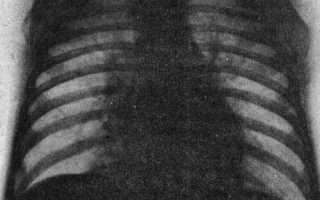

Гистологические изменения стенки тонкой кишки при аденовирусной инфекции